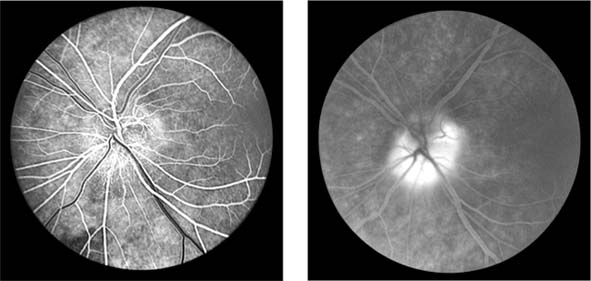

Figure 15-7

Figure 15-7: Central retinal vein occlusion. Left: Photograph shows linear hemorrhages in the nerve fiber layer and punctate hemorrhages in the deeper retinal layers. Right: Fluorescein angiogram shows dilation of the veins.

Fundus examination shows dilated tortuous veins with retinal and macular edema, hemorrhages all over the posterior pole, and cotton-wool spots. The arterioles are usually attenuated, indicating generalized microvascular disease.

The prognosis for vision is poor. Fluorescein angiography demonstrates two types of response: a nonischemic type, with dilation of retinal vessels and edema; and an ischemic type, with large areas of capillary nonperfusion or evidence of retinal or anterior segment neovascularization. In 93% of ischemic and 50% of nonischemic central retinal vein occlusions, the ultimate visual acuity is less than 20/200.

Figure 15-8

Figure 15-8: Retinal branch vein occlusion. The affected segment of retina shows changes of reduced perfusion. This results in irregularity of the arterioles and veins, areas of capillary closure, and dilated capillaries with microaneurysms.